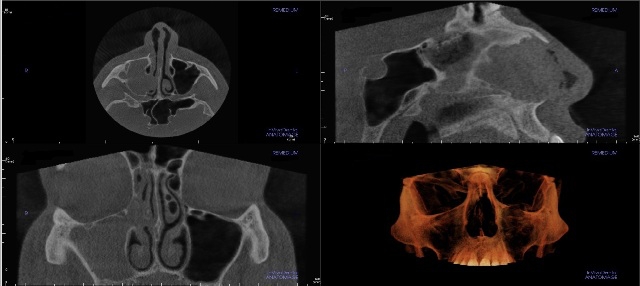

Tomografia

to zaawansowane badanie obrazowe, które wykonuje się m.in. w diagnostyce zębów oraz zatok przynosowych. Dostarcza bardzo szczegółowych danych, które mogą być cyfrowo przetworzone na trójwymiarowe obrazy. Jest wyjątkowo przydatna we współczesnej endodoncji, niezbędna w planowaniu leczenia implantologicznego oraz projektowaniu uśmiechu w protetyce stomatologicznej.